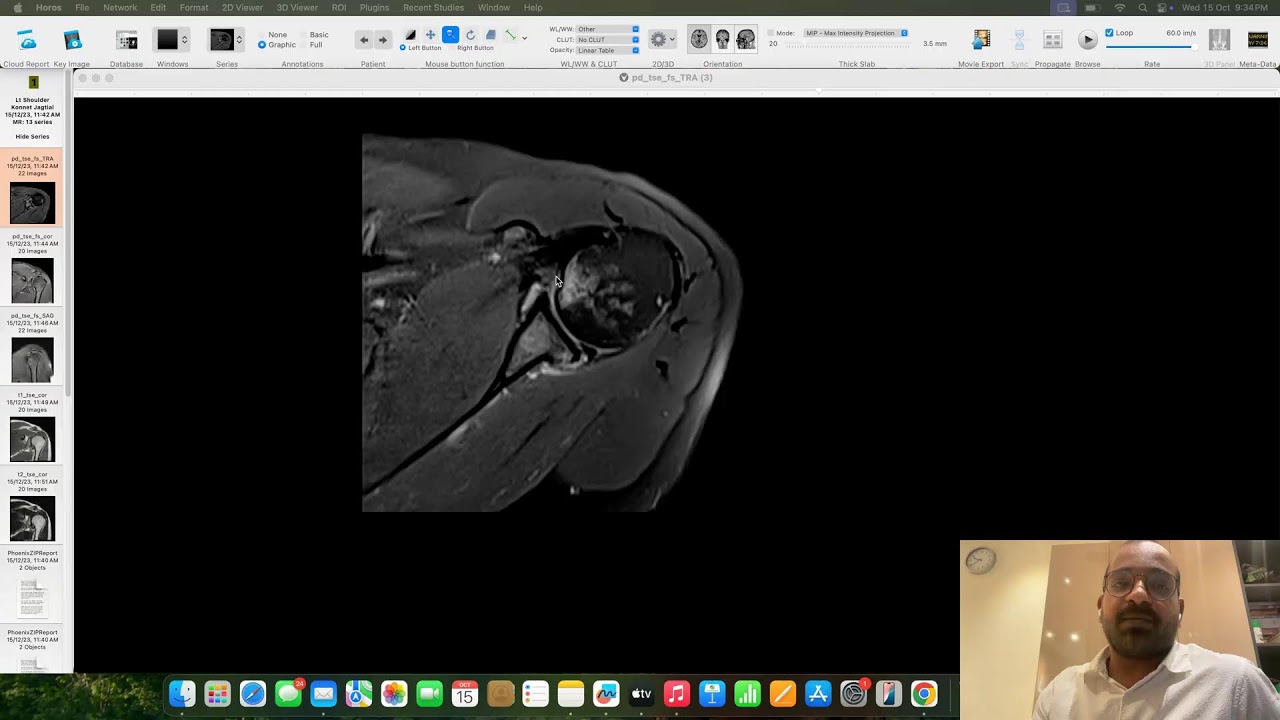

MSK CASE DISCUSSION 2*